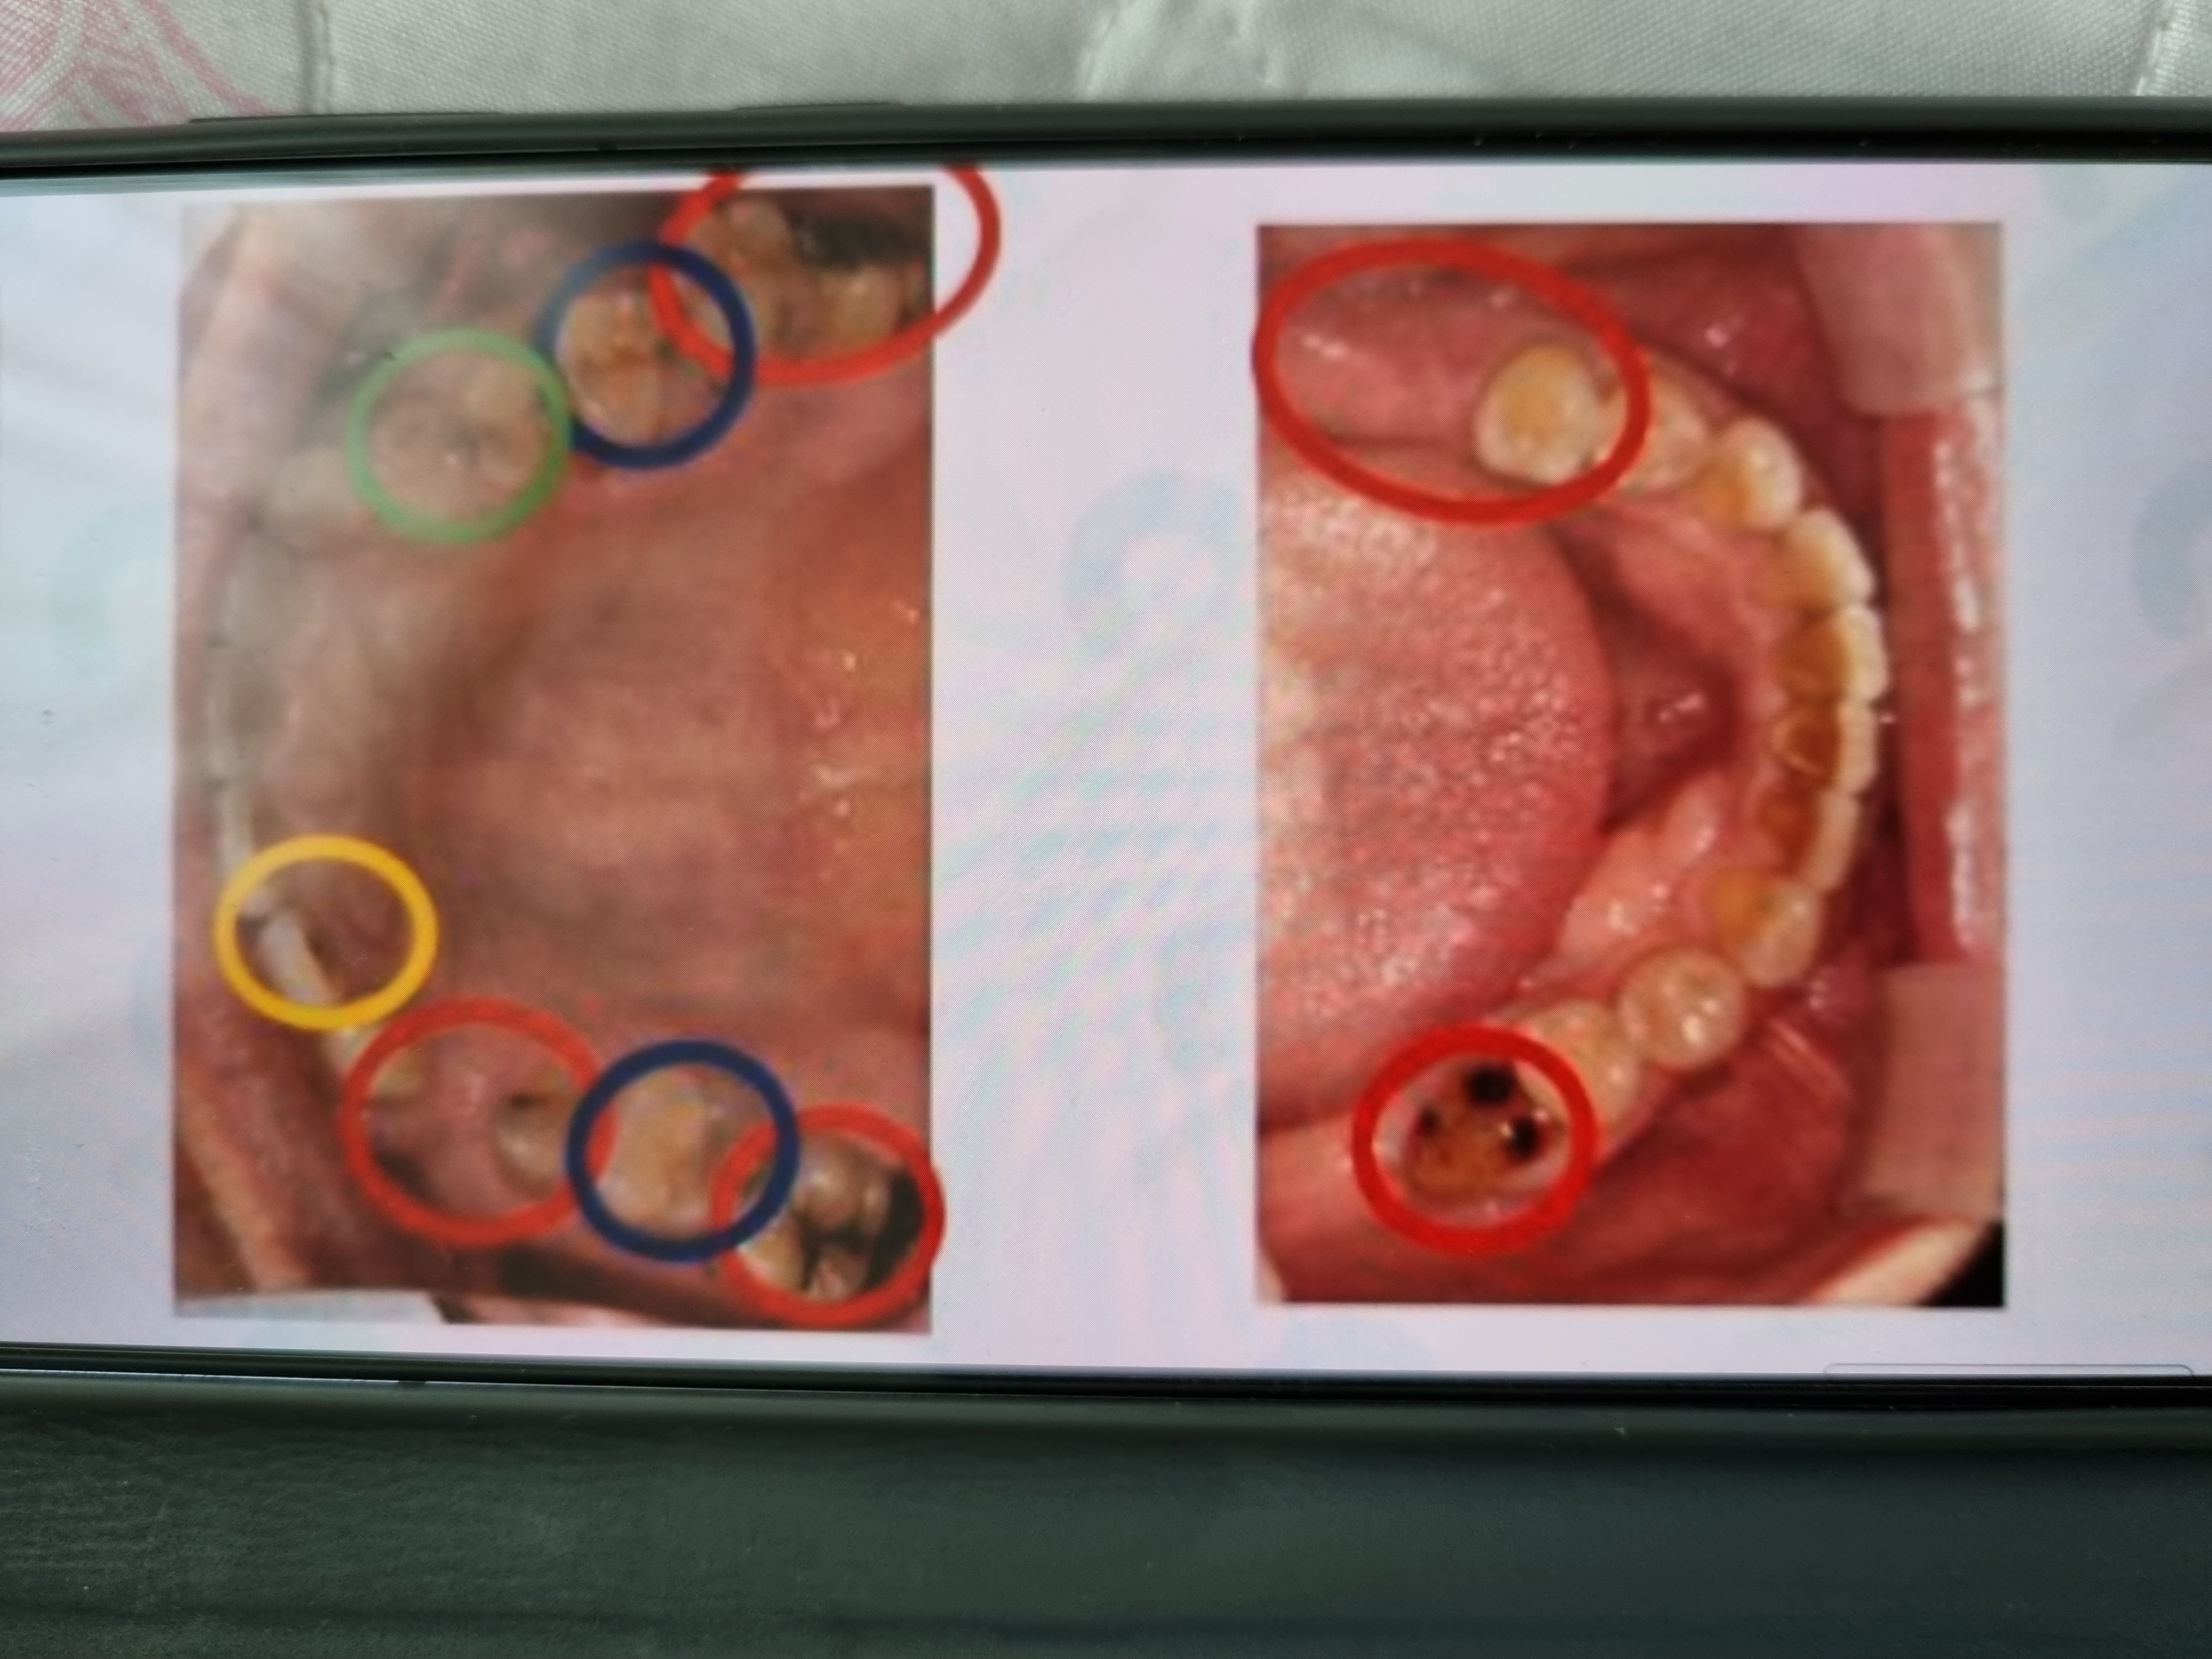

예약을하고 가게되면 기다릴 필요없이 바로 치아 촬영후에 상황을 알려주는데요. 친절하고 꼼꼼하게 촬영한사진을 본인과 함께 치료계획을 잡아주시고 부담없이 시간조욜 하게 일정도 맞춰주신답니다. 소소하게 디테일한점은 화장실에 칫솔과 치약이 있어 진료전 양치하고 상쾌하게 정밀하게 체크검사 할수있었던점이 좋았어요 감사합니다